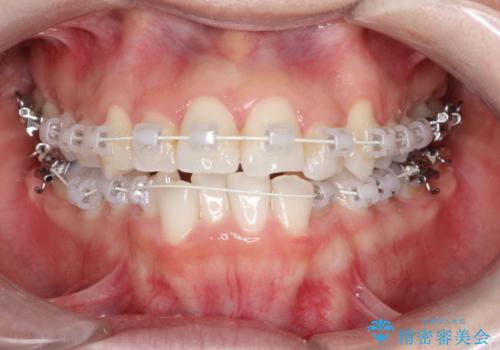

【ワイヤー矯正】前歯の凸凹を非抜歯で治療

- 前歯の凸凹を主訴に来院されました。

側方拡大にてスペースを作ることにより綺麗に前歯を並べることができました。

前歯の凸凹がある場合は治療計画を立てる上でスペースをどのように作るかが重要になります。

今回の場合は主に側方拡大でスペースの確保を行いました。